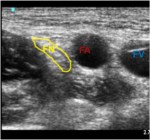

- Femoral Nerve Block – Identifying the femoral nerve prior to block